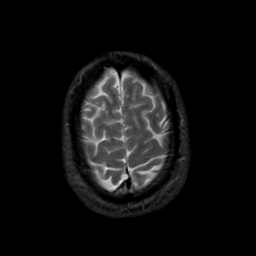

MR Study #21, November 3, 1991 -- Slice #43

[Home][Help][Clinical][Tour 1][Tour 2] Slice 43